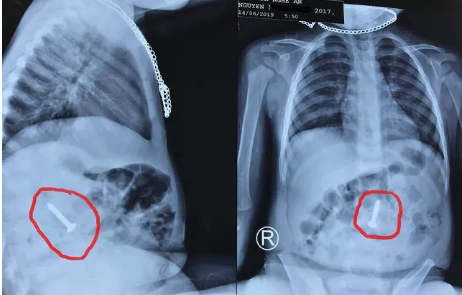

Gắp dị vật kim loại đâm xuyên amidan bệnh nhi hơn 1 tuổi

PLBĐ - Bệnh viện Nhi Trung ương cho biết, Bệnh viện vừa gắp thành công dị vật là sợi thép nhỏ nhưng rất cứng và nhọn đã đâm xuyên qua amidan khiến bé hơn 1 tuổi bị ho, nôn kèm máu.